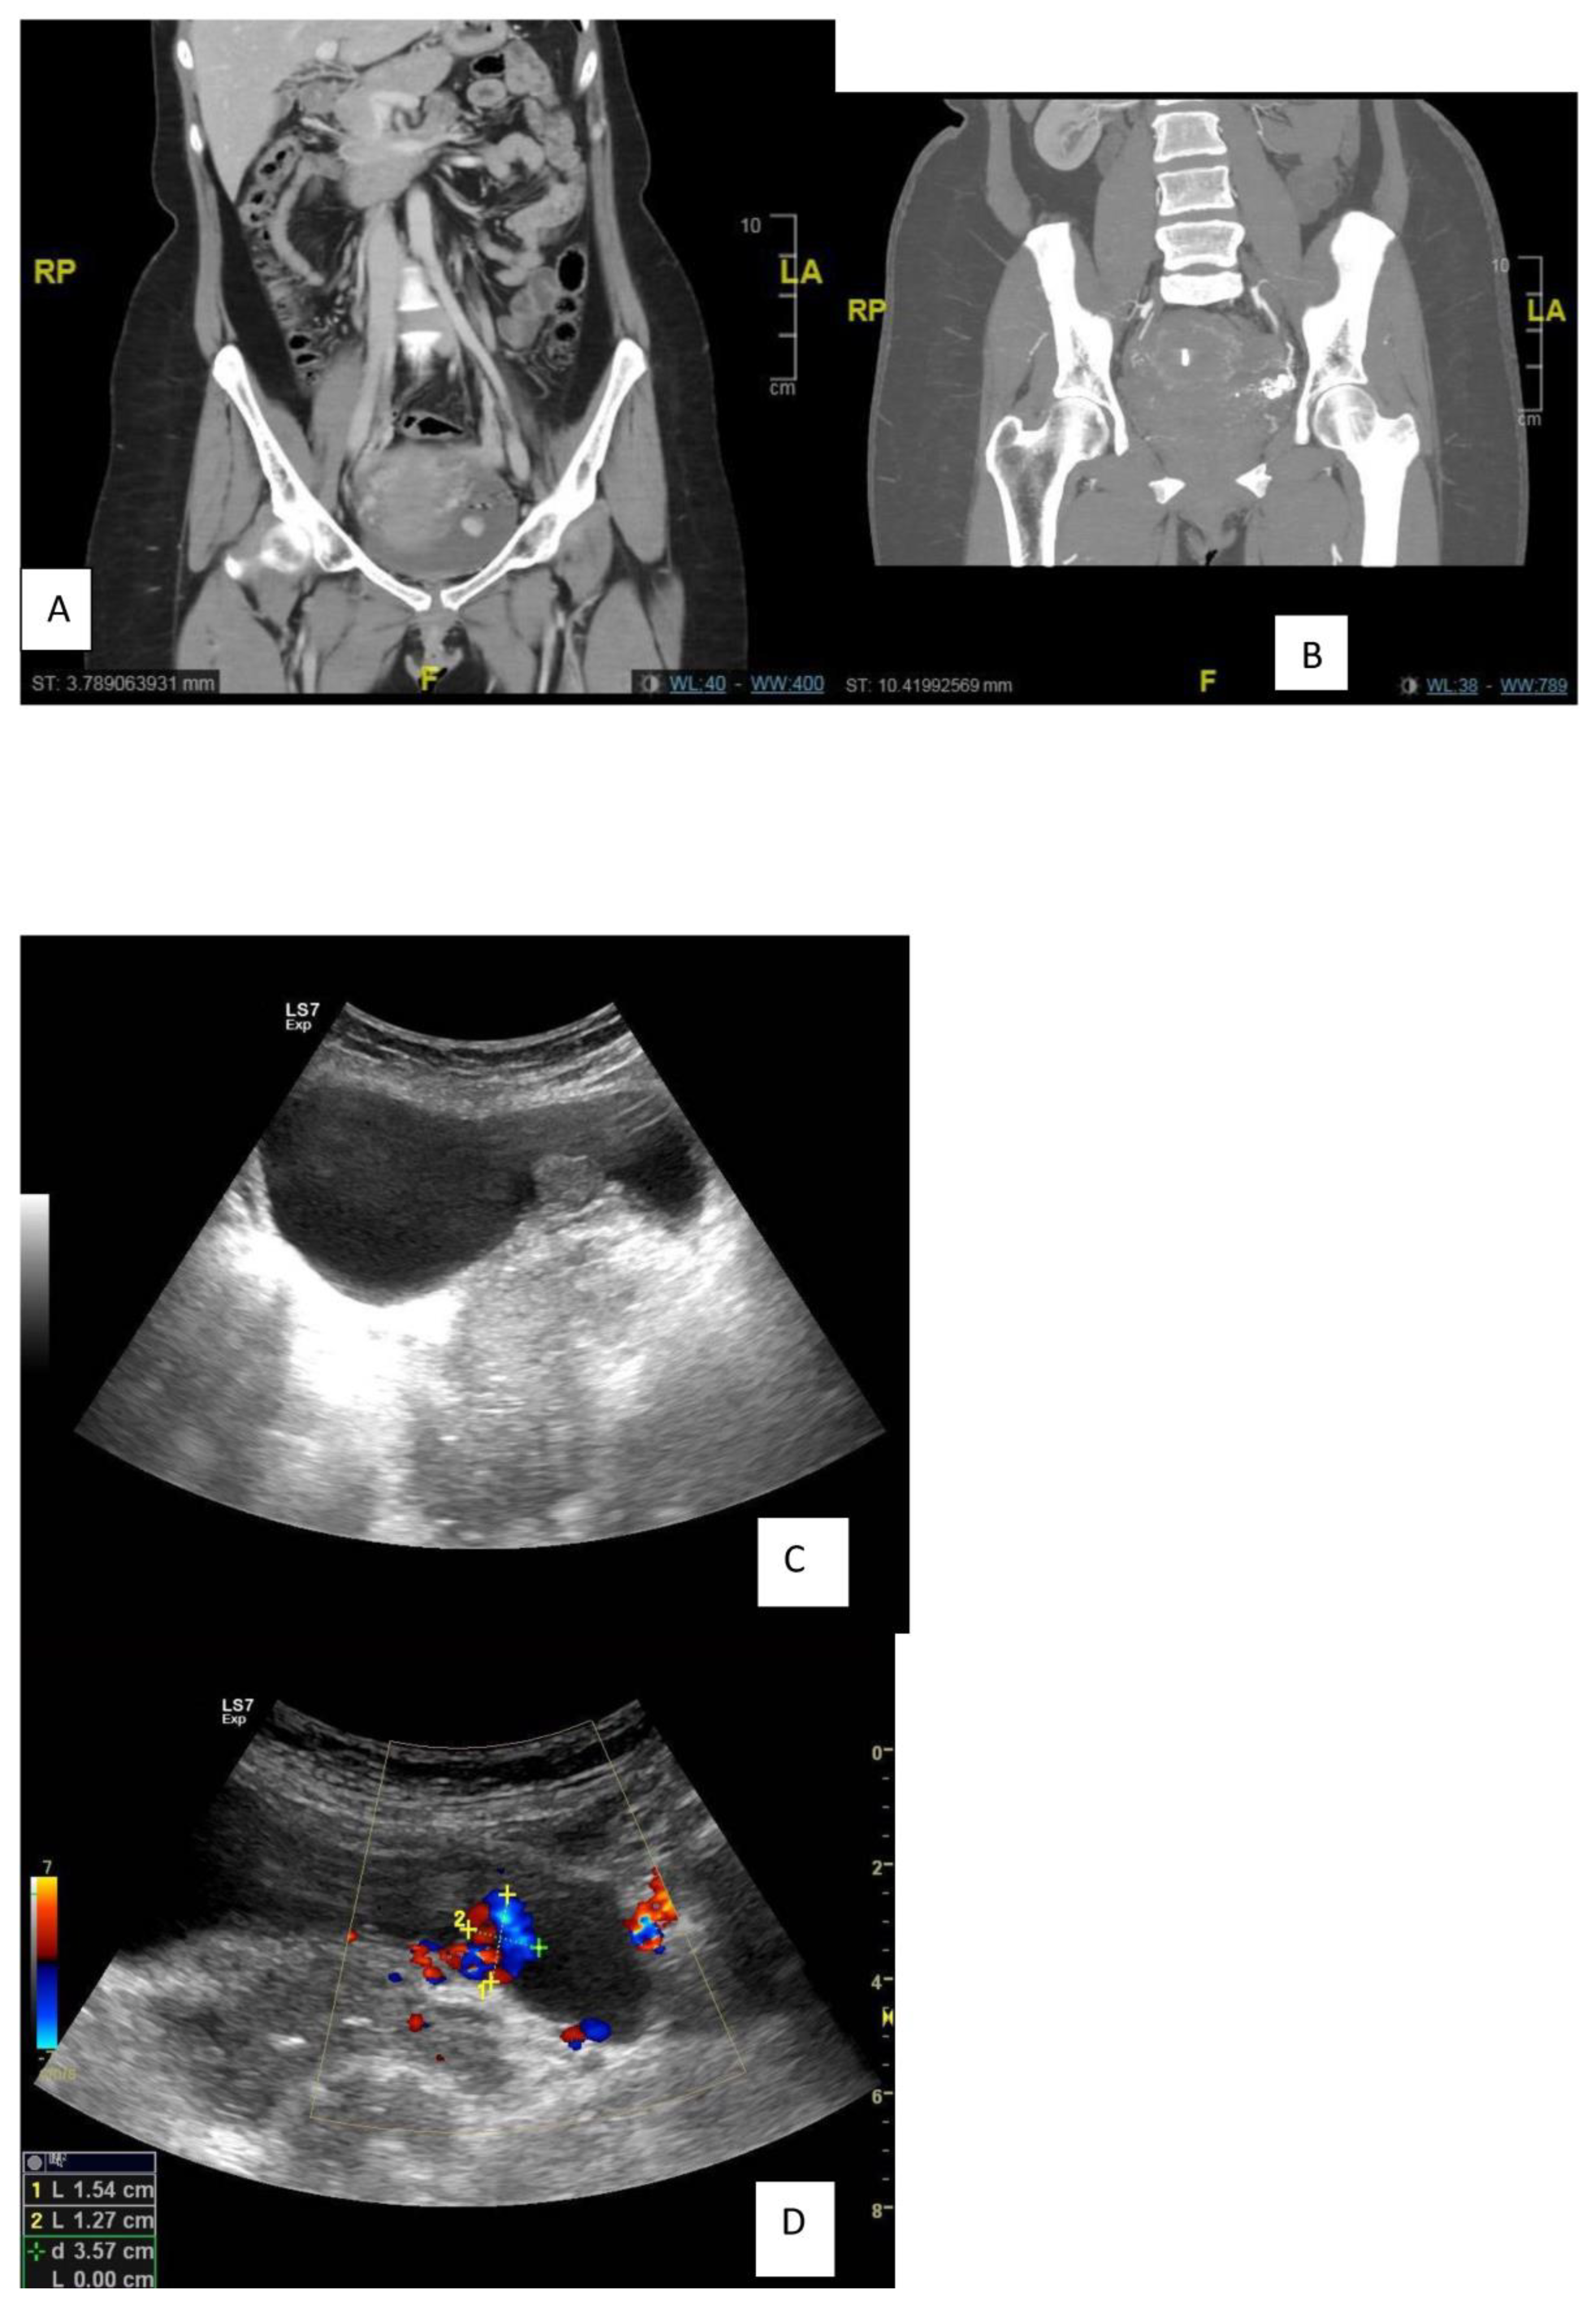

| In 2018, recurrence after 5 years of follow-up | US showed a distended UB with a polypoidal soft tissue mass measuring 16 × 16 mm with internal vascularity, nidus in afferent and efferent vessels, and turbulence in the flow. |

| In 2018, second angioembolization | The patient underwent selective catheterization of the left internal iliac artery using a C2 angiocatheter; selective angiography revealed recanalization of the previously embolized left superior vesical arteries from the anterior division of the left internal iliac artery and supplying the known intra-resulting AVM. Selective catheterization of the left superior vesical artery using a 3F microcatheter, followed by embolization of the artery, was executed using ONYX. |

| In 2022, 5 years after the second angioembolization | Ultrasonography every six months without recurrence, hematuria, or LUTS. During this period, the patient had a successful pregnancy for the second time. |